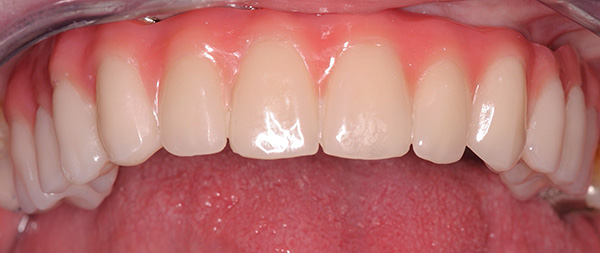

Os resultados das próteses usando a tecnologia All-on-4 parecem esteticamente agradáveis - exemplos são mostrados nas fotos a seguir.

Exemplo 1, antes do tratamento:

Após o tratamento: